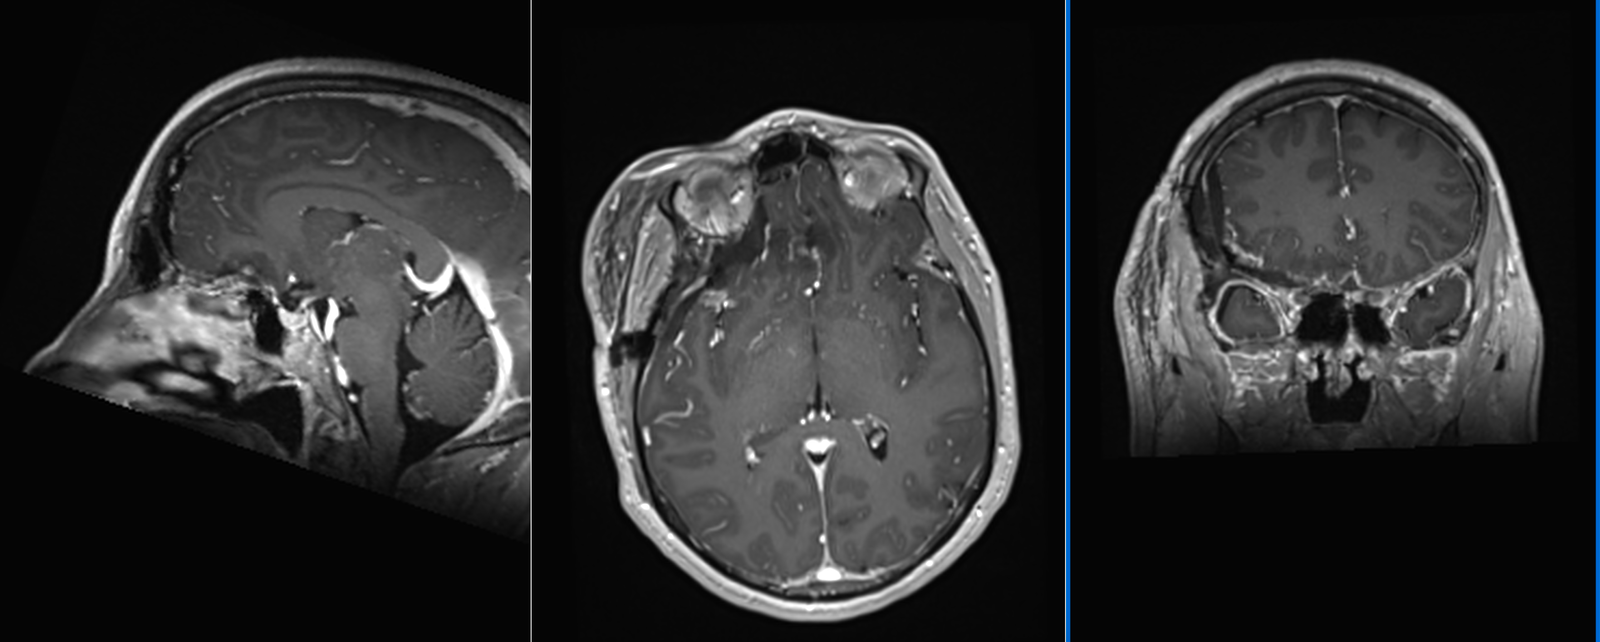

Meningiom de tubercul selar

- RMN – cea mai completă investigație, oferă detalii despre relația cu țesutul cerebral, vasele de sânge și nervii Captarea substanței de contrast este deosebit de importantă.

- CT – de obicei doar ca primă investigație. Meningioamele sunt vizibile mai ales la administrarea de substanță de contrast. Permite evidențierea afectării osoase (distrucție – osteoliză sau îngroșare – hiperostoză), a calcificărilor intratumorale precum și a rețelei venoase (angio-CT)